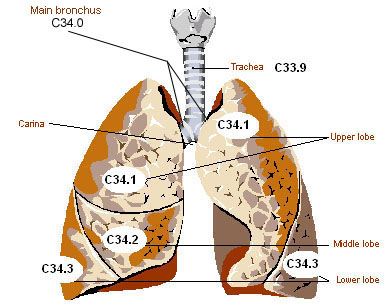

Malignant neoplasm of lower lobe, right bronchus or lung. C34.31 is a billable/specific ICD-10-CM code that can be used to indicate a diagnosis for reimbursement purposes. The 2019 edition of ICD-10-CM C34.31 became effective on October 1, 2018.

Oct 01, 2021 · Malignant neoplasm of lower lobe, right bronchus or lung 2016 2017 2018 2019 2020 2021 2022 Billable/Specific Code C34.31 is a billable/specific ICD-10-CM code that can be used to indicate a diagnosis for reimbursement purposes. The 2022 edition of ICD-10-CM C34.31 became effective on October 1, 2021.

Oct 01, 2021 · C34.91 is a billable/specific ICD-10-CM code that can be used to indicate a diagnosis for reimbursement purposes. Short description: Malignant neoplasm of unsp part of right bronchus or lung The 2022 edition of ICD-10-CM C34.91 became effective on …

Oct 01, 2021 · Malignant neoplasm of lower lobe, left bronchus or lung 2016 2017 2018 2019 2020 2021 2022 Billable/Specific Code C34.32 is a billable/specific ICD-10-CM code that can be used to indicate a diagnosis for reimbursement purposes. The 2022 edition of ICD-10-CM C34.32 became effective on October 1, 2021.

2022 ICD-10-PCS Codes 0BTF*: Lower Lung Lobe, Right. ICD-10-PCS.

A primary malignant neoplasm that overlaps two or more contiguous (next to each other) sites should be classified to the subcategory/code .8 ('overlapping lesion'), unless the combination is specifically indexed elsewhere.

All neoplasms are classified in this chapter, whether they are functionally active or not. An additional code from Chapter 4 may be used, to identify functional activity associated with any neoplasm. Morphology [Histology] Chapter 2 classifies neoplasms primarily by site (topography), with broad groupings for behavior, malignant, in situ, benign, ...